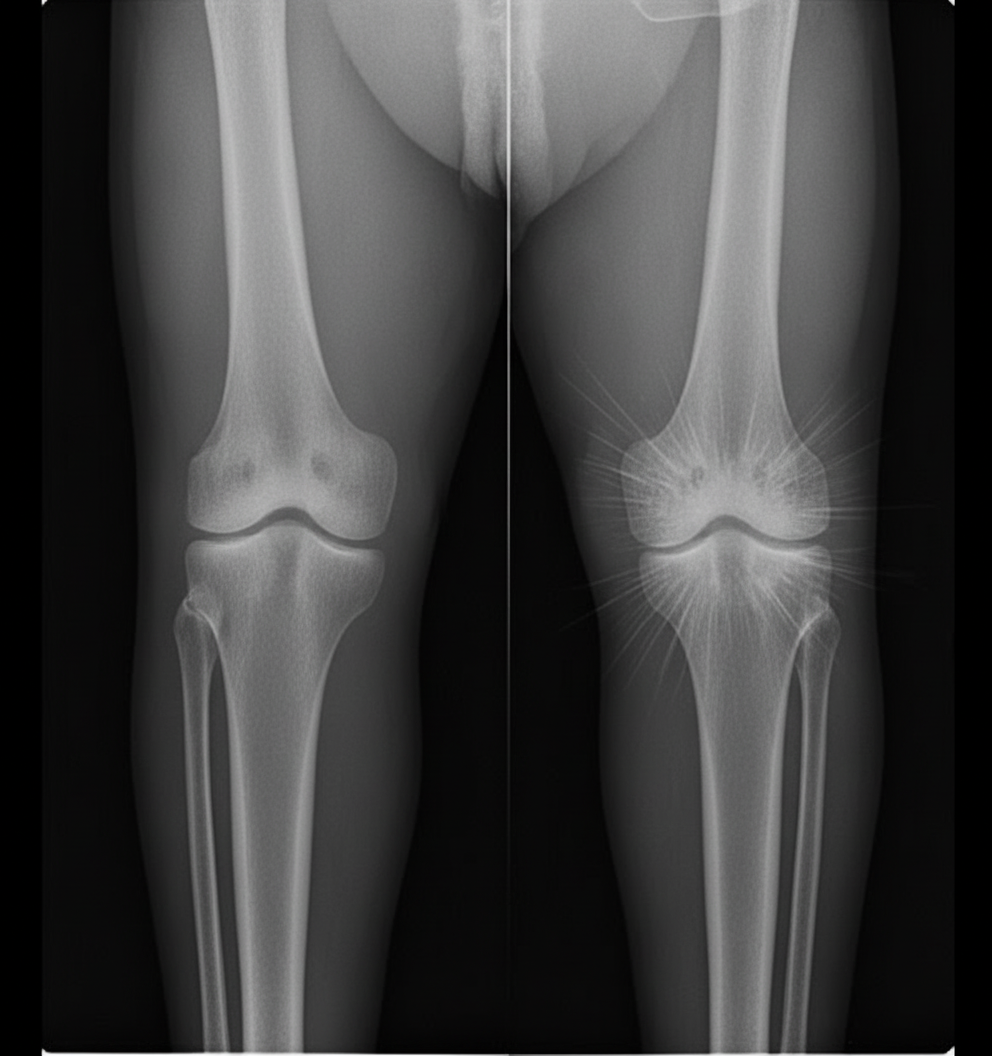

A 25-year-old male presents with right knee swelling of one month duration. A radiograph is provided. Which of the following statements is true regarding this condition?

Explanation: ***All of the above.*** - All three statements accurately describe **osteosarcoma**, the most common primary bone malignancy in young males presenting with knee swelling. - The combination of being a **bone-forming malignant tumor**, showing **Codman's triangle** on radiographs, and having propensity for **pulmonary metastasis** are classic features of osteosarcoma. *It is a bone-forming primary malignant tumor of bone.* - **Osteosarcoma** is indeed the most common primary **bone-forming malignant tumor**, typically affecting the **metaphysis** of long bones. - It predominantly occurs in **adolescents and young adults** (10-25 years), especially around the **knee** (distal femur, proximal tibia). *Codman's triangle can be seen.* - **Codman's triangle** is a classic radiographic sign formed by **elevated periosteum** at the edge of a bone lesion, commonly seen in osteosarcoma. - It represents **reactive new bone formation** where the periosteum is lifted by the underlying aggressive tumor growth. *Hematogenous spread with lung metastasis are common.* - **Pulmonary metastasis** occurs in approximately **80-90%** of osteosarcoma cases via **hematogenous spread**. - **Chest CT** is mandatory in staging as **lung metastases** significantly affect prognosis and treatment planning.